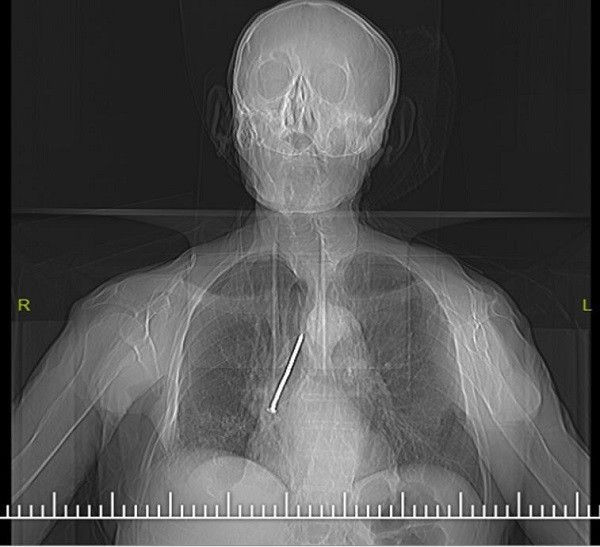

Elazığ'da yaşlı adamın boğazından 10 Santimetrelik çivi çıkarıldı - Resim: 1

Elazığ'da, boynundan nefes borusuna açılan açıklık aracılığıyla solunumunu sağlayan Keko Ateş (91), öksürük ve nefes darlığı şikayetiyle Fethi Sekin Şehir Hastanesine başvurdu. Burada yapılan tetkik ve muayeneler sonucu yaşlı adamın nefes alıp verdiği boşluğu temizlemek için kullandığı 10 santimetrelik çivinin soluk borusuna kaçtığı belirlendi. Hayati tehlike oluşturan çivi, Göğüs Cerrahi Uzmanı Dr. Öğretim Üyesi Murat Kılıç tarafından “Rijit Bronskoskopi” işlemi ile çıkarıldı.

Hızlı bir şekilde müdahale edilmediği takdirde hayatı tehlikeye atabilen bir durumla karşı karşıya kaldıklarını belirten Dr. Kılıç, "Larenks kanseri nedeniyle 24 yıl önce boynundan nefes borusuna açılan açıklık aracılığıyla nefes alıp verebilen hasta, nefes borusundaki bu açıklığı temizlemek amacıyla kullandığı 10 santimlik çiviyi soluk borusuna kaçırmış.

Bu nedenle gelişen öksürük ve nefes darlığı şikayeti ile önce başka bir sağlık merkezine başvurmuş, ardından Fethi Sekin Şehir Hastanemiz Göğüs Cerrahisi Kliniğine yönlendirilmiş. Biz de hastanede 91 yaşındaki hastamıza çektiğimiz tomografide soluk borusu içerisinde, sağ akciğer içerisine doğru kaçmış olan çiviyi tespit ettik” dedi.